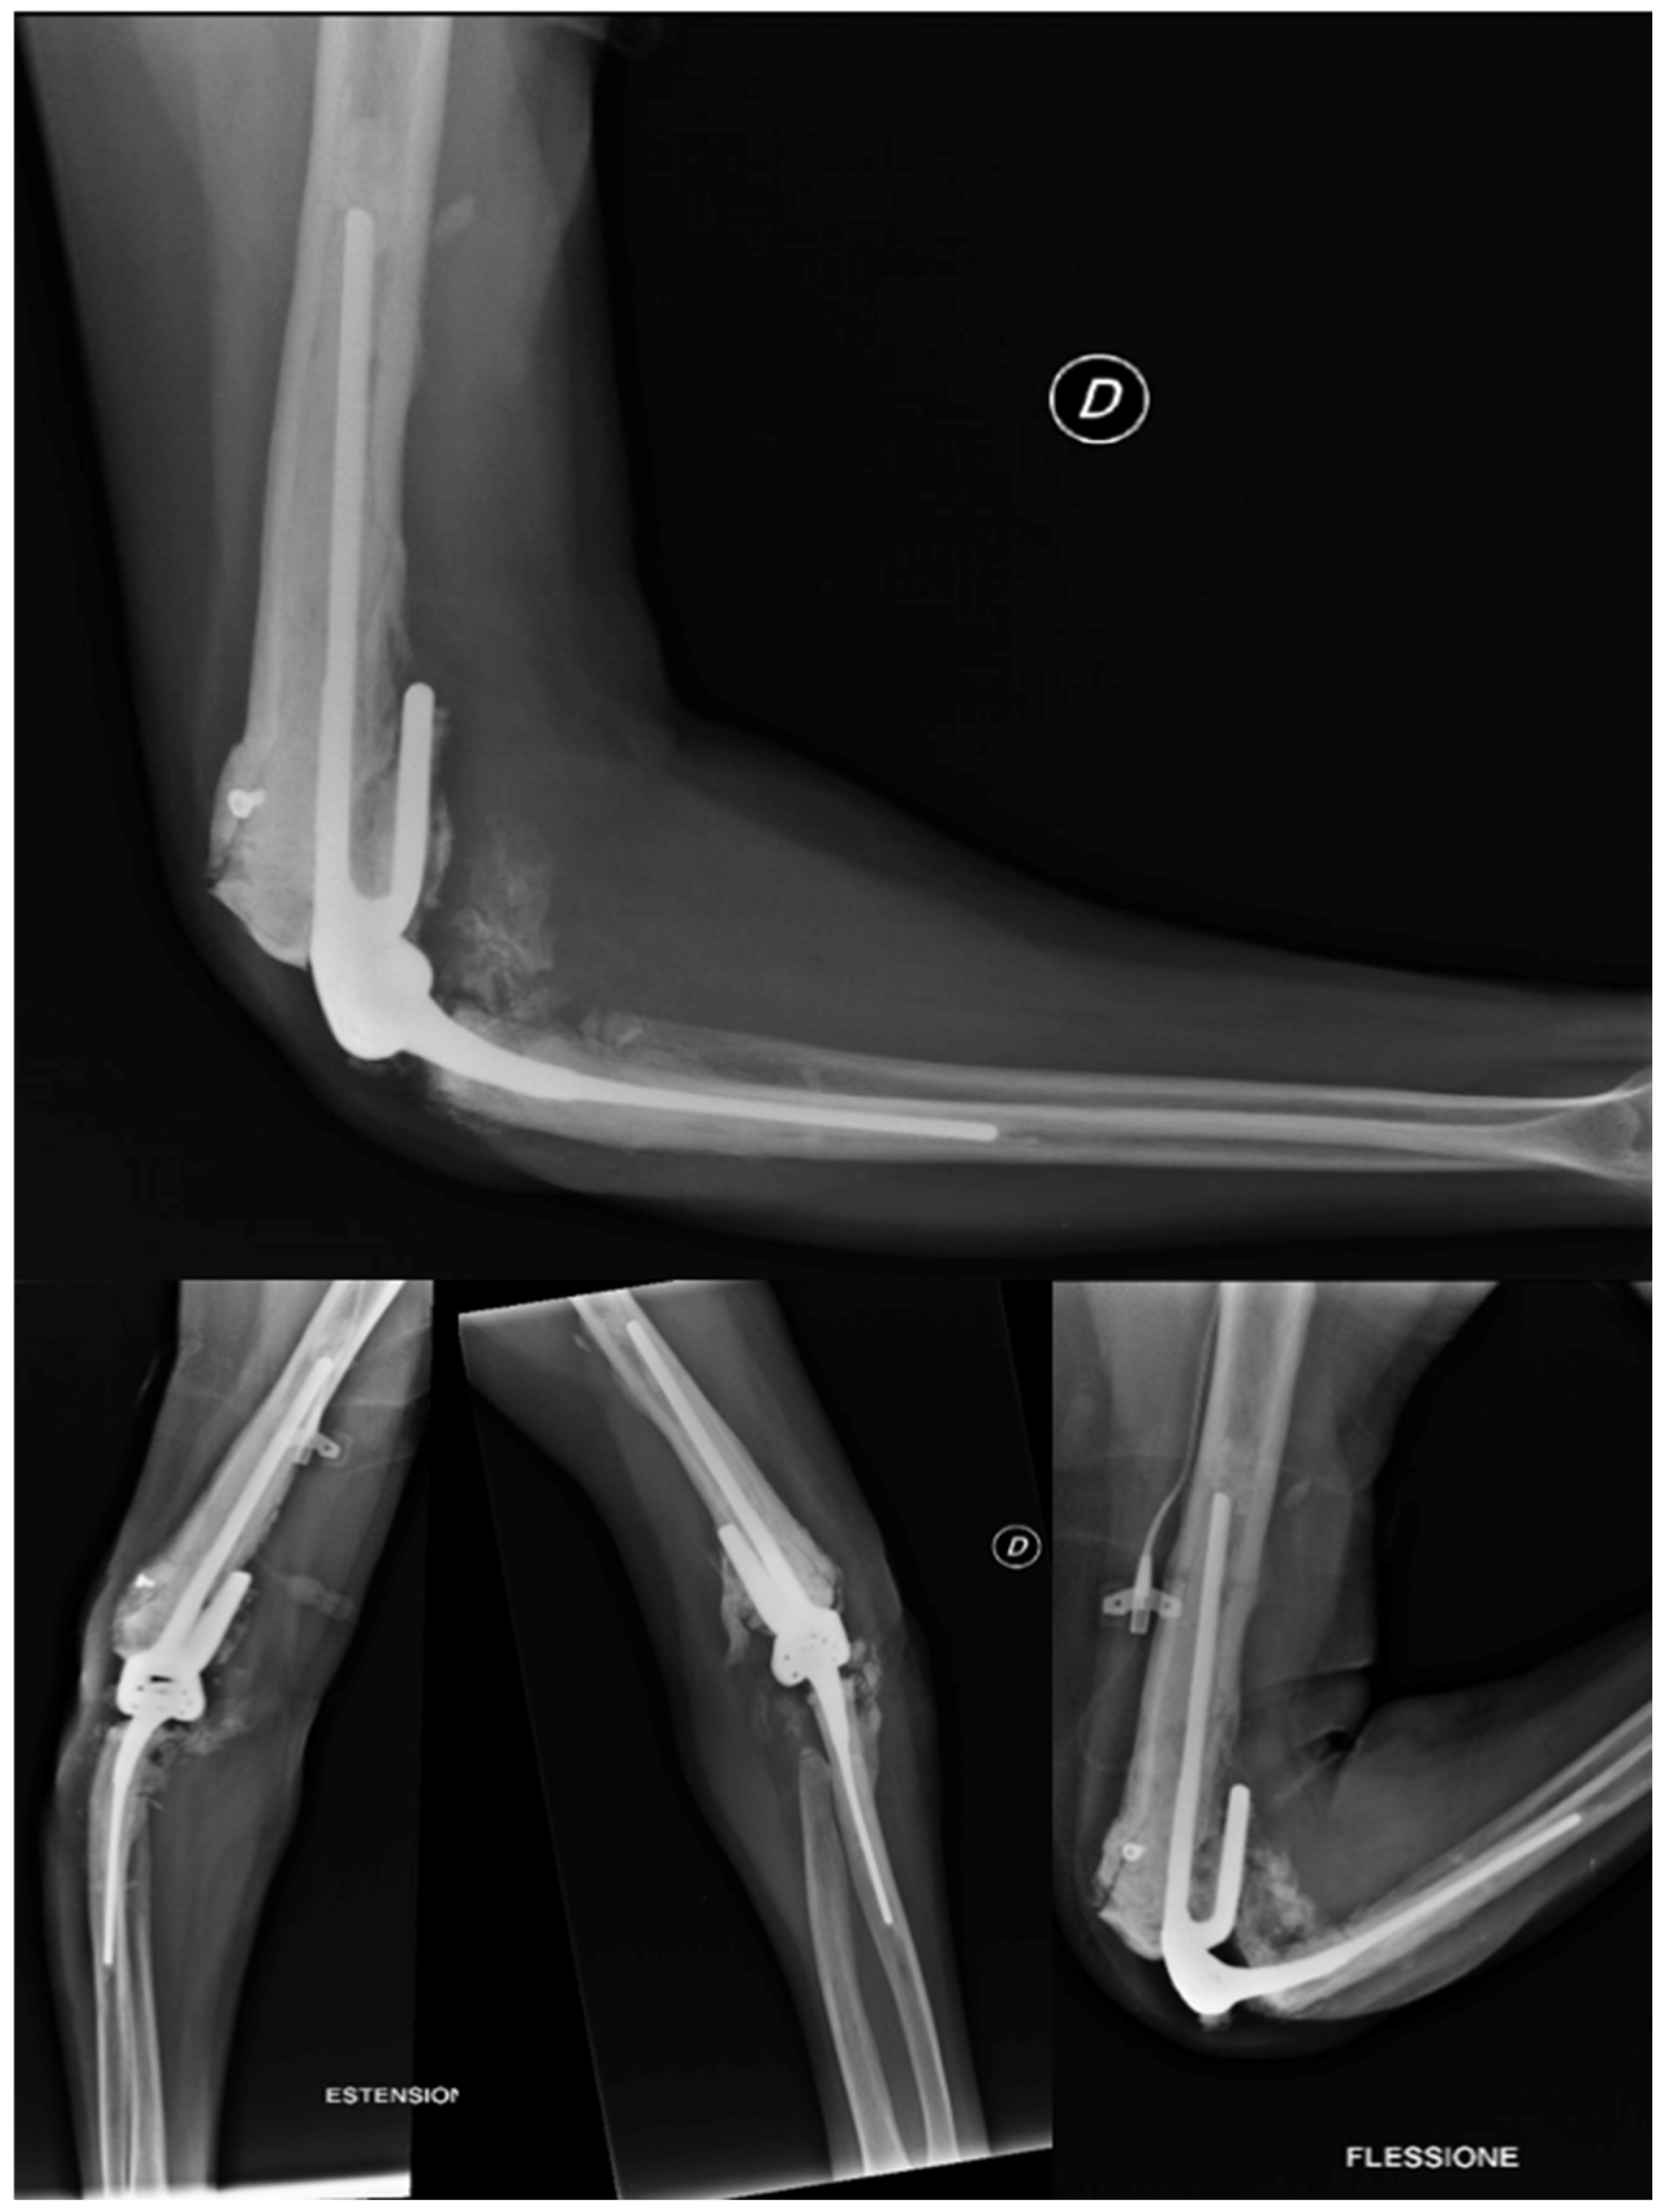

2.4.5. Total Elbow Arthroplasty

- Evidence from the Scientific Literature

Total Elbow Arthroplasty and Complications

2.4.6. Revision Total Elbow Arthroplasty